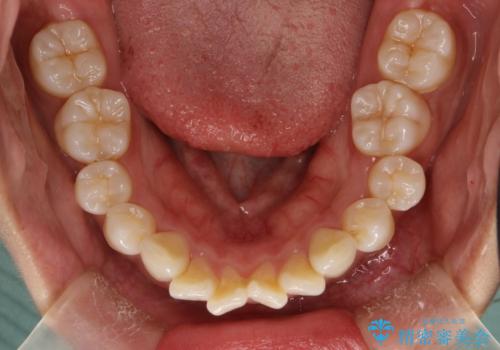

がたがたをインビザラインで整った歯並びへ

- 全体的ながたつきを主訴に来院されました。

抜歯矯正も考えられる状態でしたが、患者様が非抜歯での矯正を希望されたため、歯と歯の間をわずかに削りスペースを作り、全体を整える計画としました。